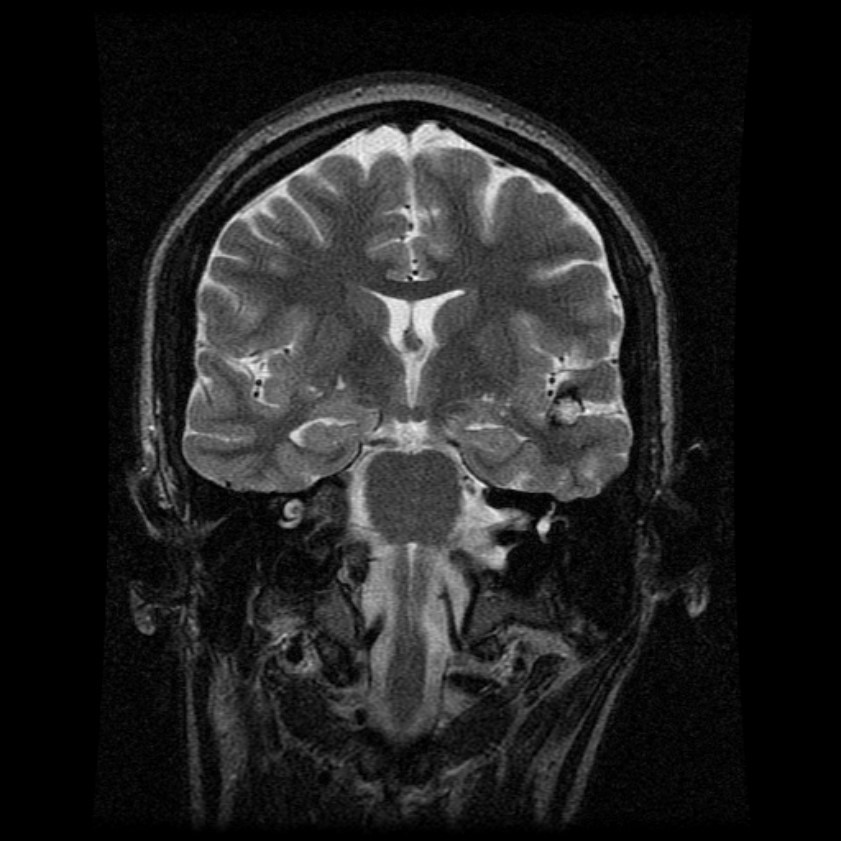

Neuroradiological Investigations

MRI

Hypocampal sclerosis